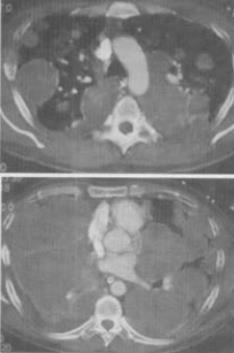

- 单项选择题 男,33岁,咳嗽1周,有骨肉瘤病史,结合CT,最可能的诊断是()。

- C